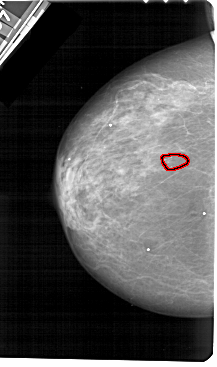

A_1176_1.LEFT_MLO

FILE: A_1176_1.LEFT_MLO.OVERLAY

TOTAL_ABNORMALITIES 1

ABNORMALITY 1

LESION_TYPE CALCIFICATION TYPE FINE_LINEAR_BRANCHING DISTRIBUTION LINEAR

ASSESSMENT 5

SUBTLETY 4

PATHOLOGY MALIGNANT

TOTAL_OUTLINES 1

BOUNDARY